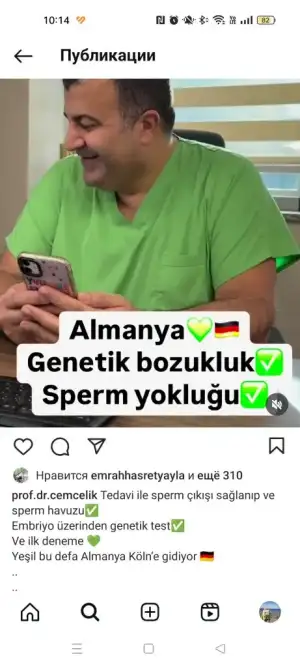

Kuzum gecmiş olsun.Şimdi her şeye çare var bak bu doktor geçen paylaşmış sperm hiç yokmuş bence dene istersen çok övüyorlar bu doktoruKızlar beni hatırladınız mı bilmiyorum afranın başkan olduğu gruptaydım hepinizi az çok hayırlıyorum. Kadınlar kulübü bile bilmezdim evlendim ilk ay buraya girdim ve bir gruba ilk ve tek girdiğim grup. Afra hamile kalmaya çalışıyordu ve hamile kalmıştı o ara grupta aktiftim.. Henüz 2 aylık falan evliydim 2023 temmuzda.. Ben de sıkıntı yoktu ama hemen istiyordum sizinle bir ovülasyon testleri yaptırdım eşime kendime kürler yaptım. Hele o çörek otu kürü vardı hergün zorla yiyordumregl her şeyim düzgündü 24 yaşındaydım. Ama niyeyse hem benim olmuyor diye düşünüyordum. 8 ayın sonunda hastaneye gittik kontrol ettirdik bende her şey normal hatta ilk aydan hamile bile kalırmışım o kadar iyimiş durumum ama neye yarar. Eşimde azospermi çıktı sperm 0... Hemde en zoru sebepsiz olanı.. Genetik hormonlar temiz sıkıntı yok ama spermde yok işte. Meğer aylarca uğraş boşa.. Üstüne 10 ay tedavi gördü eşim şehir şehir gezdik en son İstanbula gittik 5 saat uzak bize.. Ben tüp bebek tedavisi gördüm sperm çıkarsa diye eşim ameliyata ama o da yarım kaldı sperm bulunamadı

Bakayım canım ya. Bizim doktorda çok iyidi ama işteKuzum gecmiş olsun.Şimdi her şeye çare var bak bu doktor geçen paylaşmış sperm hiç yokmuş bence dene istersen çok övüyorlar bu doktoru